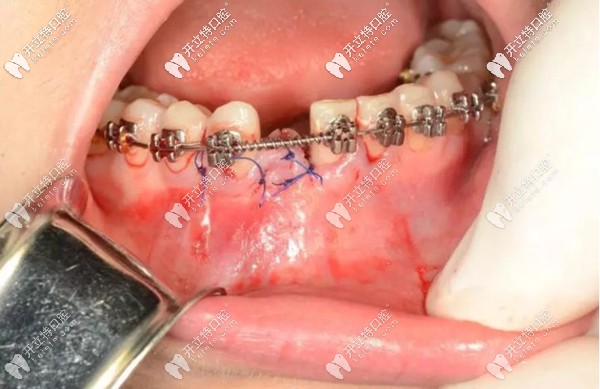

然后,將種植手術(shù)部位進行縫合,靜待植體和牙槽骨的結(jié)合,預(yù)計3個月左右的時間。之后安裝基臺、牙冠,這顆種植牙大概需要半年左右的時間才能“大功告成”。

而做種植牙這段時間,對我的牙齒正畸治療也不會有太大影響。